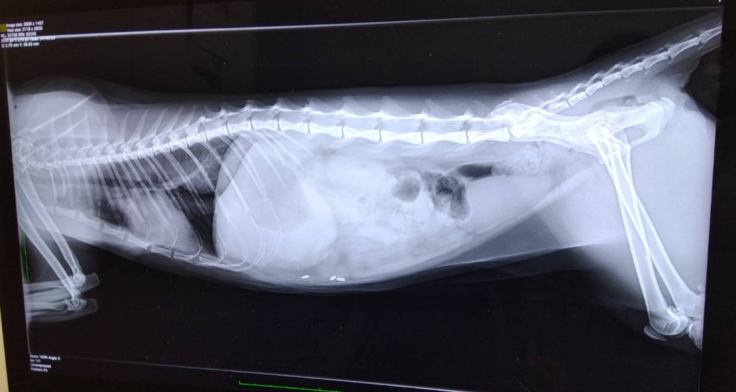

腸の病気や気になることを伝えて、触診と聴診器で診てもらってレントゲンを撮ってもらいました。

胃と大腸にガスがたまってるとのこと。

他にも気になる腸の病気や合併症の可能性、自律神経失調症や過剰摂取などもあるんじゃないかと聞いてしまいましたが、レントゲンでは分からないので、まずはこのガスを出す治療をと。

はなちゃんの場合、ずっとアンモニアが高い状態なのもあり、肝内シャントなので予後も命にかかわりますとおっしゃられました…

腸閉塞の可能性はなさそうだというのが分かっただけでも。。